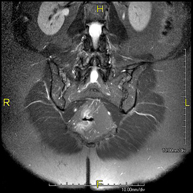

This non-invasive diagnostic procedure uses an electromagnetic field and radio waves (from a transmitter and receiver) to acquire high-definition anatomical images of the lumbar and sacral regions. It is a radiation-free procedure. Indicated for: trauma, sciatica, herniated discs, tumours, infections.